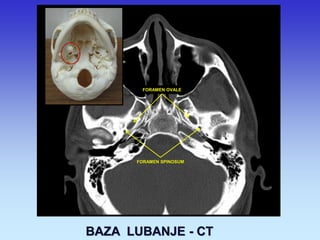

BAZA LUBANJE - CT

FORAMEN OVALE

FORAMEN SPINOSUM